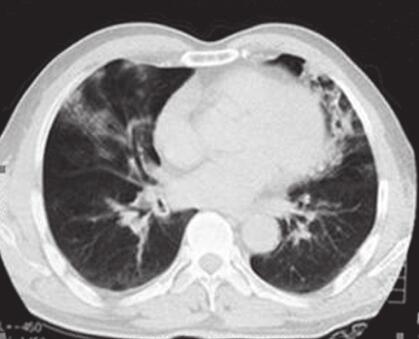

患者,男,48岁,农用车司机。因“咳嗽、胸痛、气促10天”于2012年3月3日入院。患者10天前修汽车后,突然出现反复咳嗽、咳痰,偶见痰中带血,伴有右侧胸痛、活动后气促,曾于当地医院行胸部CT(图1)检查发现“两肺炎症改变”,先后给予“头孢美唑、头孢哌酮舒巴坦钠”抗感染等对症支持治疗,症状无改善。2012年2月29日复查胸部CT示肺部病变范围扩大,并出现发热,后给予“阿奇霉素、头孢吡肟”等药物治疗,患者仍感胸闷,咳较多白黏痰,为求进一步诊疗,入住我科。

图1 2012年2月21日胸部CT示双肺炎症改变